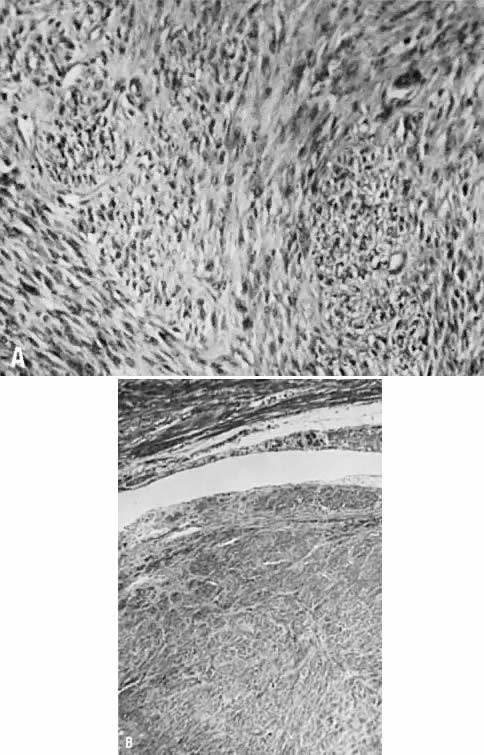

Uterine leiomyomas are usually spherical masses of tissue that can vary from a few millimeters to many centimeters in diameter. They may grow large enough to obstruct the ureters, compress the great vessels, or compromise of pulmonary ventilation. On dissection, myomas appear to have a capsule. The cells on the edge of the tumor seem to become flattened in the concentric pattern, leading to the clinical impression of a capsule, although there is no distinct fibrous tissue capsule microscopically (Fig. 1). Nevertheless, the pseudocapsule layer is the preferential plane of dissection to peel out the main mass of the myoma from the surrounding, more normal myometrium. The blood supply enters at the periphery of the tumor and the core is relatively avascular, which is the probable reason for the various forms of degeneration and necrosis that are seen in the center of some myomas.

Fig. 1. A. Intramural leiomyoma with whorled arrangement of smooth muscle cells on a matrix of connective tissue cells (×200). B. Notice the absence of distinct connective tissue capsule (×175). ( A and B, 66% of original magnification.)